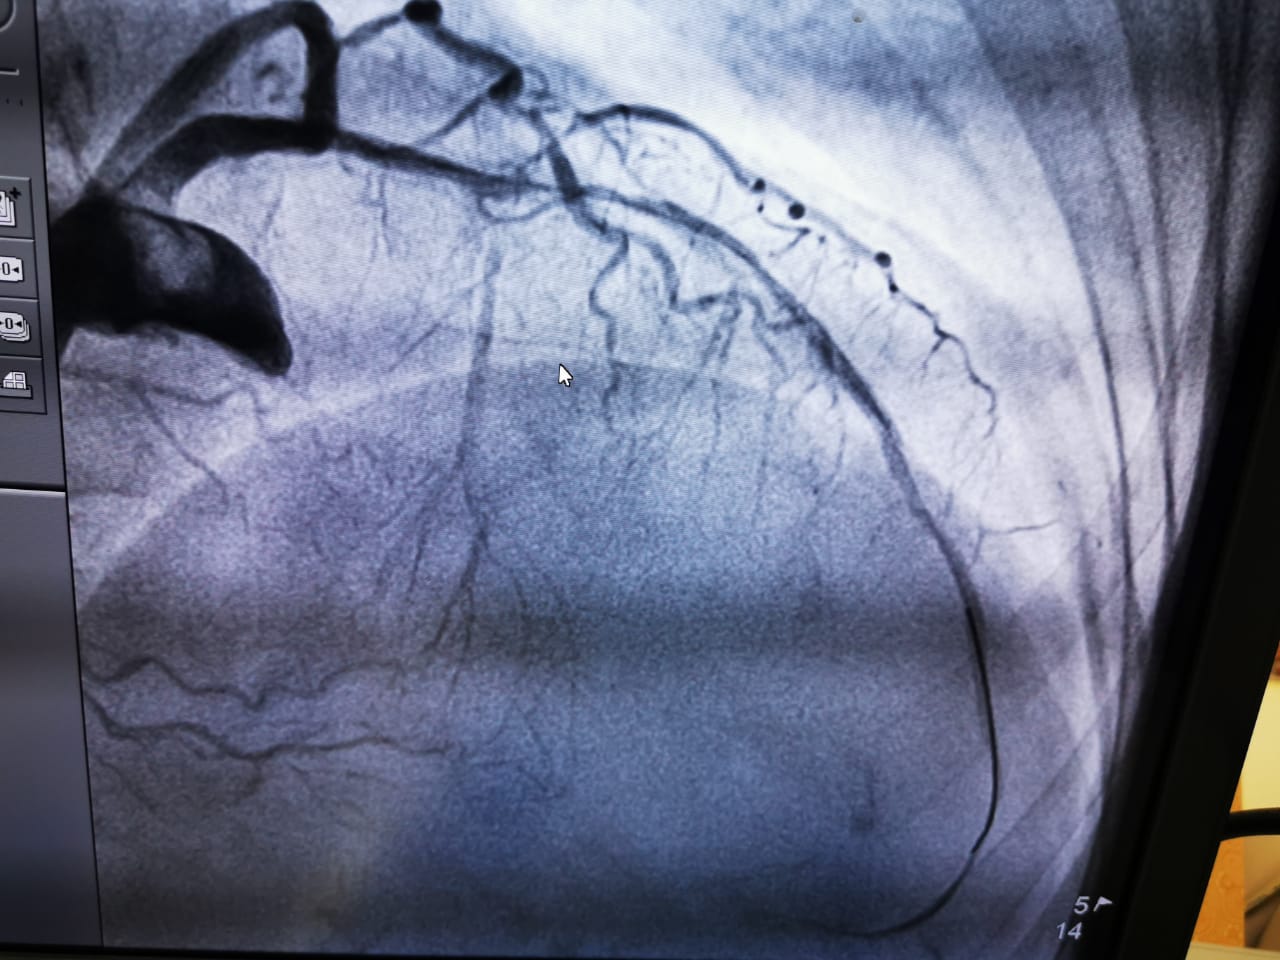

It gives us immense pleasure to have witnessed India’s First laser atherectomy (Lad uncrossable with balloon, Laser 0.9 and 1.4 ELCA) at JNM hospital Raipur chattisgargh with Dr Smit Srivastava, proctored by Dr. Arun Kalyanasundaram. We thank everyone who participated in this event and made it possible!